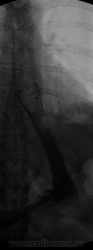

Исследование проведенное сегодня:

Это продолжающееся осложнения фундопликации по Ниссену, на первой серии снимков видно затек  в поддиафрагмальном пространстве брюшной полости с  н/3 пищевода, т.е. сформировался свищ, да ещё и кожный, именно поэтому совместно с эндоскопистами, они первоначально установили проводник и далее под контролем уже R-скопии, установили стент, я же попросил сделать глоток водорастворимого контрастного вещество перед окончательной установкой стента, как видно на предпоследней  серии свищевой ход остался в стороне, ну и сегодня мои коллеги сделали контроль, как видно всё без затеков, только вот сомнения гложит по поводу уровня установки, далековато всё же получилось, надо было чуточку на себя подтянуть.

Ох уж эти шаловливые хирурги. Виталий, а Вы здорово провели исследование! Стент если подтягивать, то совсем немного, а то лучшее - враг хорошего. Сделайте контроль через недельку - стент и сам может чуть подвинуться вверх-вниз

Сейчас уже его ни как не подтянуть, а у Вас таким добром Татьяна Валентиновна не пользуются? МЫ 2й раз только устанавливаем данный стент, вообще они предназначены как бы для онко-пациентов, со стенозирующим раком пищевода.